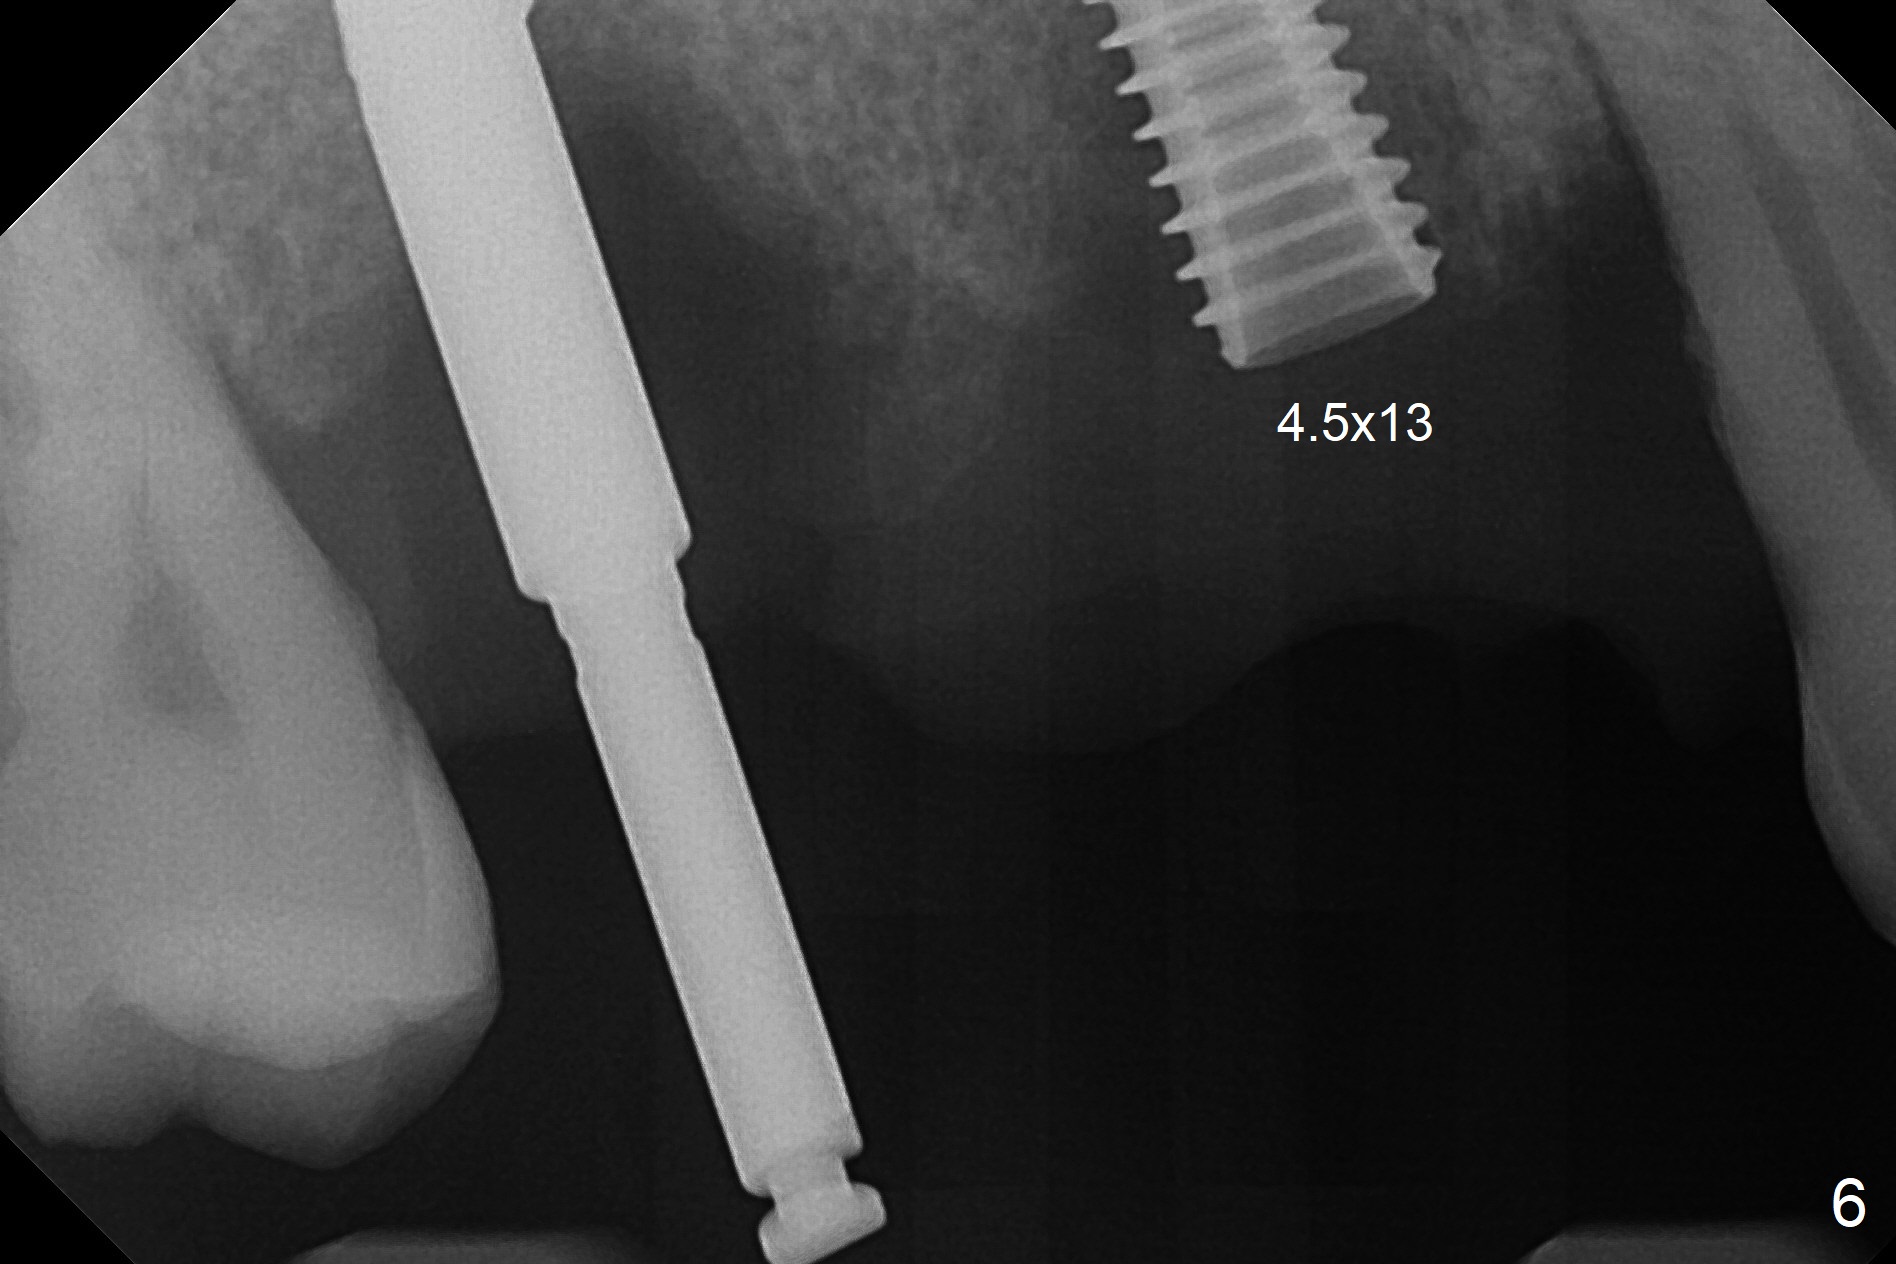

The 36-year-old man (ex-smoker, quit for 4-5 years) insists upon #3 and 5 extraction first for implants, in spite of more severe infection at #7, 14,19,30 (Fig.1-4). The gingiva around #23-26 implants is healthy 3 weeks postop (Fig.5). The initial depths at #3 and 5 are 8.5 mm (bone-level) and 18 mmm (gingiva-level (13 mm (implant length) + 5 mm cuff), respectively. When a drill penetrates the sinus floor, confirm the depth. After use of 3.8 mm drill, 4.5 mm tap drill is inserted at #3 without stability, while a 4.5x13 mm implant is placed at #5 with primary stability (Fig.6,7). Then a 5x11.5 mm is placed at #3 subcrestal proximally after sinus lift with Vanilla graft (without sinus membrane perforation; Fig.8). The implant at #5 is seated ~1 mm deeper (subcrestal mesially (^^); supracrestal distally (^)); allograft is placed around the implants prior to insertion of 6.5x7(5) and 5.5x4(5) mm abutments; last more allograft is added (Fig.9 *, 10). The implants seem to have been osteointegrated 4.5 months postop (Fig.11,12). The gingiva is healthy around the implants without bone loss 3 months post cementation (Fig.13,14).